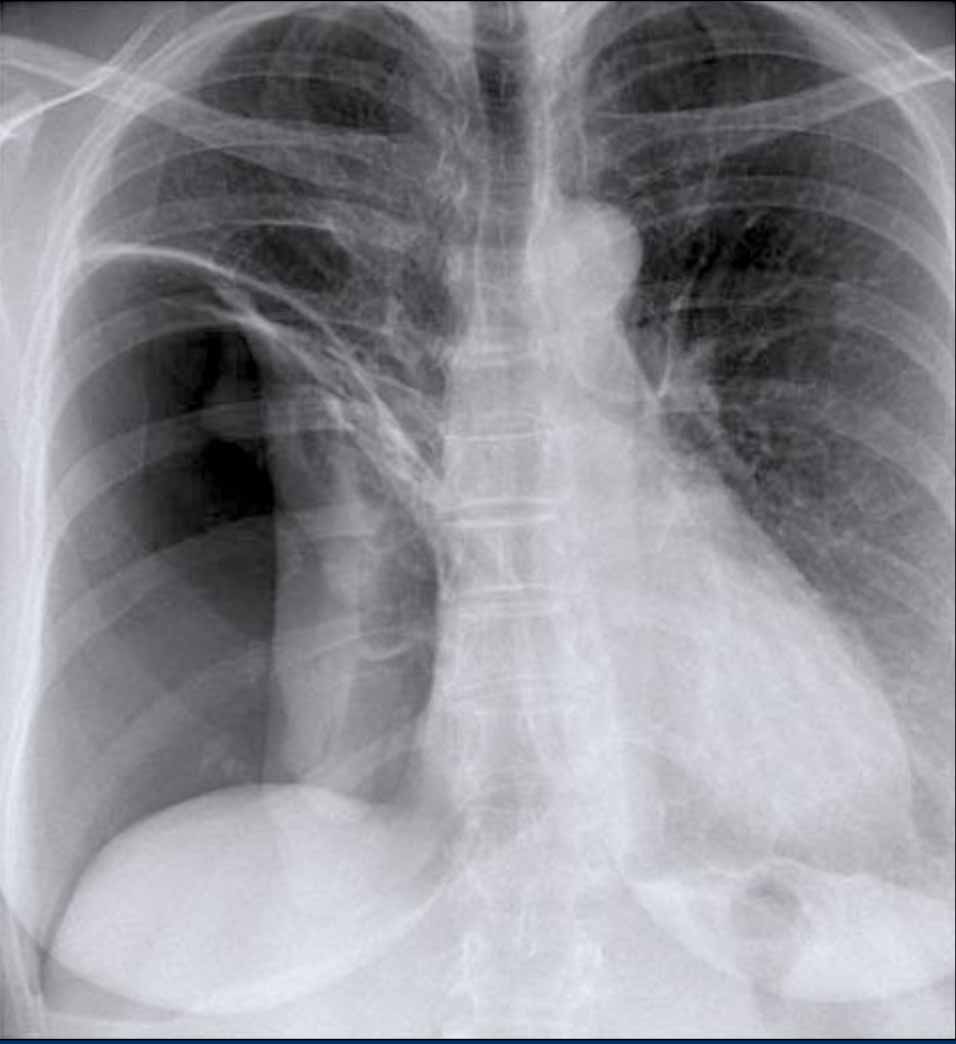

Case Example: Subtle Signs of Congestive Heart Failure

Begin by reviewing these current chest radiographs.

Based solely on these images, one might suspect congestive heart failure (CHF), though the findings are subtle.

Now review the previous study…

Scrolling between the current and prior films significantly increases diagnostic confidence in your diagnosis of congestive heart failure.

Key comparative findings include:

• Cardiac size: Slightly increased compared to the previous study; however, cardiomegaly was already present.

• Pulmonary vasculature: Mild vascular engorgement suggesting elevated pulmonary venous pressure.

• Interstitial markings: Subtle signs of interstitial edema .

• Pleural effusions: Bilateral small effusions, with subtle changes in the inferoposterior borders of the lower lobes, suggesting fluid accumulation.